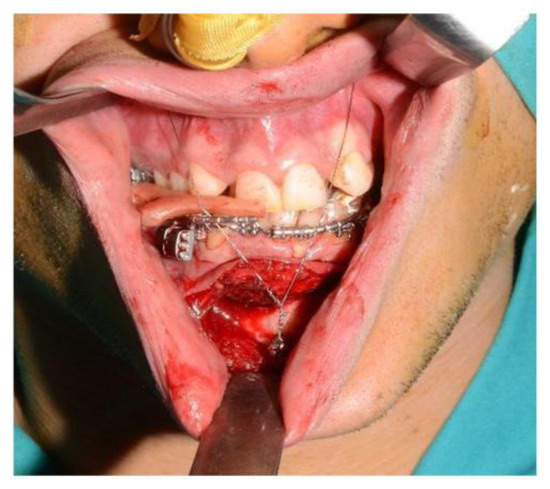

5. CASE 3: Subapical (Köle) Osteotomy in Dento-Facial Deformity

A 23-year-old patient exhibited a class III dentoskeletal malocclusion, as well as transverse and sagittal hypoplasia of the upper maxilla. Moreover, the patient presented an inclination of the teeth in the anterior mandibular sector that could not be orthodontically treated. Consequently, the following treatment plan was formulated:

- First step: SARPE (Surgical Assisted Rapid Palatal Expansion) and subapical (Köle) mandibular osteotomy, followed by subsequent distraction osteogenesis.

- Second step: LeFort I maxillary osteotomy segmented into two pieces.

For the subapical osteotomy, it was decided to use the tracked tool technique with a piezoelectric scalpel to perform the procedure and avoid the risk of dental root injury, thereby enhancing surgical precision. A maxillary bite was created, and 5 screws with different space vectors were then placed on it, serving as fiducial markers. The bite was used to ensure that, during the entire surgical procedure, the mandible maintained the same position as in the preoperative CT scan. Virtual planning was performed with careful consideration of dental root preservation in the osteotomy tracing. During the surgical procedure, the Dynamic Reference Frame (DRF) was positioned in the left parietal bone, and the screws located on the bite were used as fiducial markers. The same bite used during the acquisition of CT scan images was used. Two screws were secured onto the maxillary bone, with an additional one in the mandibular symphyseal region. Simultaneously, an intermaxillary fixation was used to replicate as accurately as possible the mandible’s position maintained during the CT scan image acquisition (Figure 8).

The piezoelectric tool was registered by anchoring the three reflective spheres to the tool’s handpiece. At the same time, the tip of the piezoelectric device was marked and used as a reference for navigation (Figure 9).

The navigation accuracy was less than 1 mm. The subapical osteotomy was performed as previously planned (Figure 10).

One week post-op, an OPT (Orthopantomography) X-ray was performed, which showed the adequacy of the osteotomy and the preservation of dental roots. Three years later, at the end of orthodontic alignment, the second surgical step was carried out (Figure 11a,b).